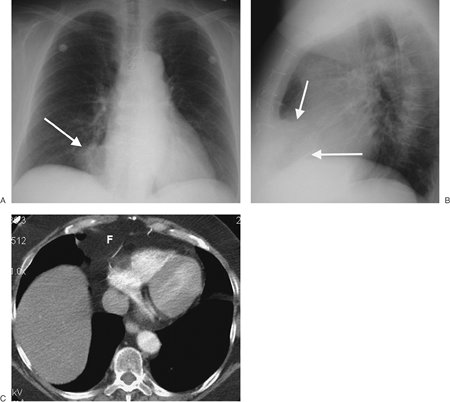

FIGURE 6-2. Prominent pericardial fat. A: Posteroanterior (PA) chest radiograph shows a round mass at the right cardiophrenic angle (arrow) that is less opaque than the adjacent heart. B: Lateral view shows that the mass is projected over the anterior inferior heart (arrows) in the typical location of pericardiac fat. C: CT shows this mass to be of fat attenuation (F), similar to that of the subcutaneous fat.